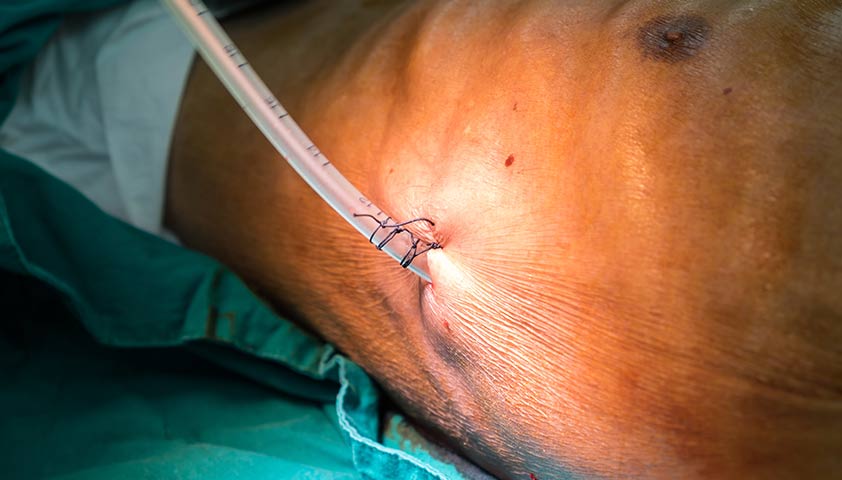

Однако если пневмоторакс большой или вызывает одышку, воздух нужно срочно удалить из плевральной полости. Делают это хирургически — с помощью пункции или дренирования под местной анестезией. Дренаж оставляют на несколько дней, пока лёгкое не расправится полностью.

Под местной анестезией в грудную клетку вводят иглу или дренажную трубку, чтобы выпустить воздух